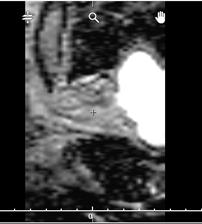

How to check: When the DICOM volume is displayed on the "Contour" page, the volume is displayed inverted on the apex-base axis. The position of the bladder is an effective reference point: "on the left", the volume is displayed correctly, "on the right", the volume is displayed inverted.

| Image displayed correctly: the bladder is on the left | Image displayed reversed: the bladder is on the right |